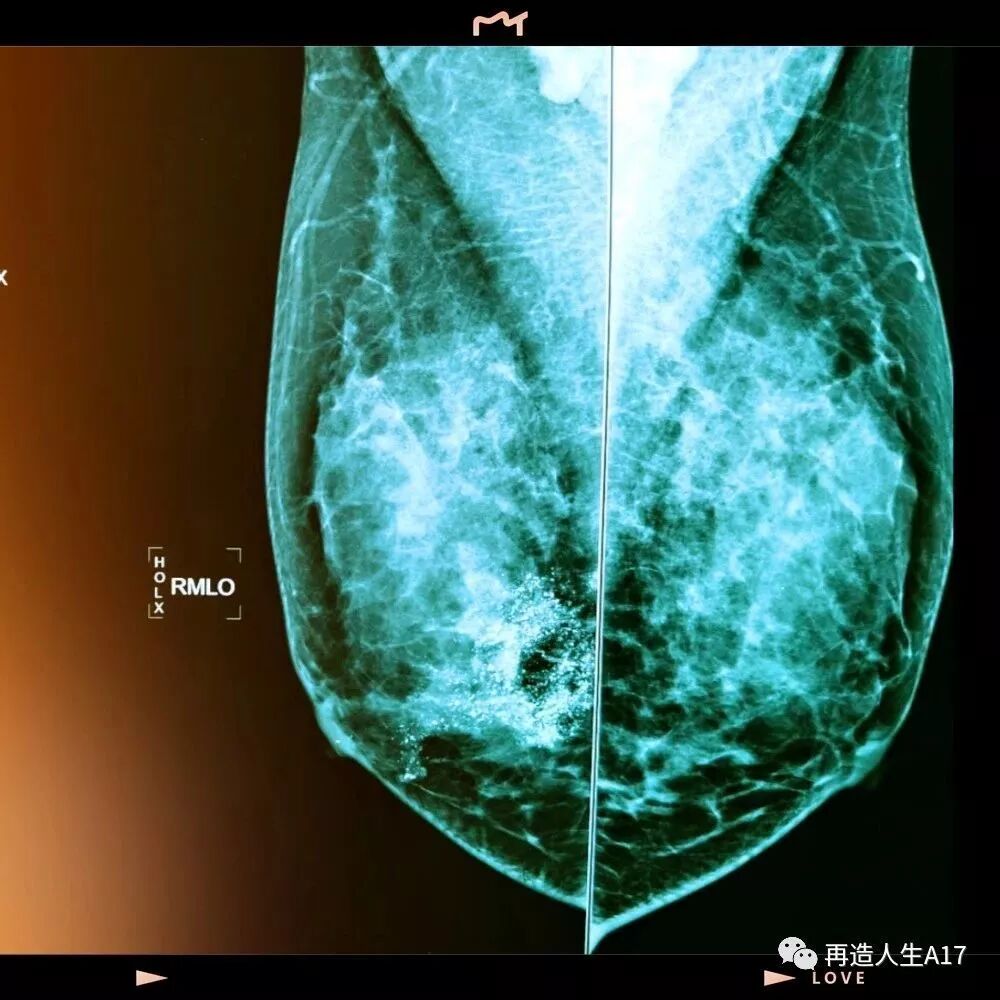

乳腺钙化一般是通过乳腺钼靶检查发现的,表现为高密度的点状影或者团块影。乳腺钙化可以分为良性钙化和恶性钙化,一般良性钙化是粗大的,散在的,而恶性的钙化一般多为模糊不定形、粗糙不均质、细小多形性及细线样或线样分支状。